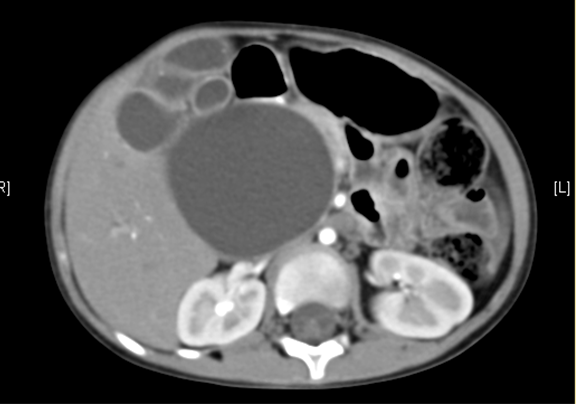

腹部CT 增强:1. 肝内外胆管扩张,考虑胆总管囊肿并胆系扩张可能性大2. 胆囊结石。

将0.625mm双源薄层CT资料的静脉期和动脉期Dicom格式文件导入海信CAS系统。

通过调节窗宽窗位调整CT序号,对肝实质,胆囊,下腔静脉,肿瘤,肝动脉、门静脉及肝静脉等进行三维重建;系统自动计算肝脏体积。

术前CT检查:

动脉期

静脉期

平衡期